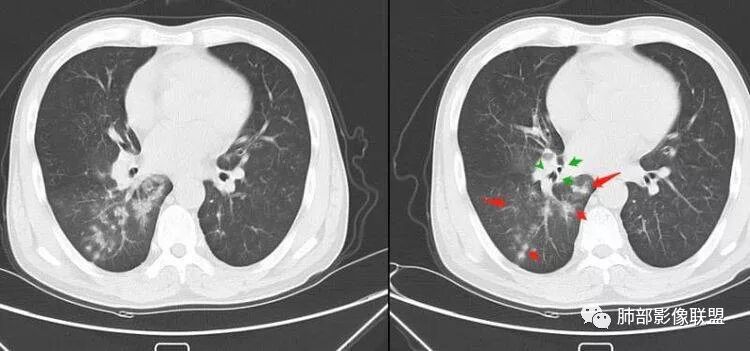

南边:紧贴着斜裂过来的一个病灶,它的特点是:外围大,内带小。它整个下叶背段体积与对侧相比稍微缩小一点,但是缩小地不是很厉害。外支朝前下走了,仔细看血管,肺动脉走行自然,直达远端。远端实变区是肉芽肿成分,稍微有一点低密度,没有明显坏死,稍微有一点点坏死。而且附近有很多卫星灶,附近很多斑片影,有一些明显有气道壁增厚,细支气管炎的特点,还有就是下叶其他段很多斑片状影。换个角度,第一如果是肺癌,刚才看到PET-CT提示肺癌伴阻塞性肺炎,这个是不符合的。第二如果是肺癌阻塞性肺炎,近端血管肺动脉走行不会那么自然集聚的,这个是不符合的。理由是:如果这个病灶是肺癌,那么明显属于中央型肺癌,中央型肺癌的特点是近端大,远端小,近端是一个肿块,远端阻塞,远端阻塞是阻塞性炎症或者不张,它应该体积缩小,斑片状实变,不会这么密实。刚才有老师提到支气管,这个片有缺陷的地方,给的图像好像那层,如果把其他图像拿开再重叠一下。

南边:这个肺门区,11区和7区都有一些淋巴结,淋巴结的形态不是类圆形,而是梭形的。这个病灶给的图比较少,个人倾向,第一强化非常均匀,肉芽肿性病变;第二,里面血管走行非常自然,远端大近端小,倾向炎性,特别是下面还有斑片状影,非阻塞远端,支气管远端病灶下叶背段,其他段也有,所以我倾向炎性;另外,它里面整个走行符合支气管树爬行征,我倾向结核可能,首先我定在炎性,其次有没有结核的可能。

鉴别诊断:肺炎性肺癌,胸膜下起源,外围大,局部占位效应,有膨隆有收缩,这个不太支持。支气管走行里面没有看到支气管进入很自然堵塞的粘液栓的特点。附近这些磨玻璃影,它的磨玻璃影要么边界清楚,要么由内朝外蔓延的,而不是沿着支气管束蔓延的。而且附近斑片状影,有些似乎有结节感,但是大部分不是,它不是我们常见的磨玻璃样结节,有些有,导致像腺泡样结节那种椭圆的沿着血管束分布的,我会把肺炎型肺癌放在待排。

初学者:小细胞肺癌会不会炎症支气管血管束这样淋巴蔓延M-Imaging :小细胞癌转移大,冰冻纵膈南边:按理周围的炎症解释不通飞鹰行动:小细胞没有见过这样没有明显转移的飞鹰行动:阻塞性炎症,结核不好解释,除非有增大淋巴结压迫支气管良孑:外大内小,支气管爬行征,邻近肺野播散灶,TB首选,没意见:多个分支都受累,如果是阻塞,那堵的部位应该在各分支的汇合处,但这例确实没看见Coke with ice:这个人第一感觉是结核。用结核不好解释的就是病灶周围的晕。

右肺下叶背断肿块,外围大,内带相对狭长         远端有膨隆,边缘模糊、凹凸不平         血管走形自然,病灶近端支气管通畅,沿支气管树蔓延         周边有多发病灶,多为磨玻璃密度且边界不清。